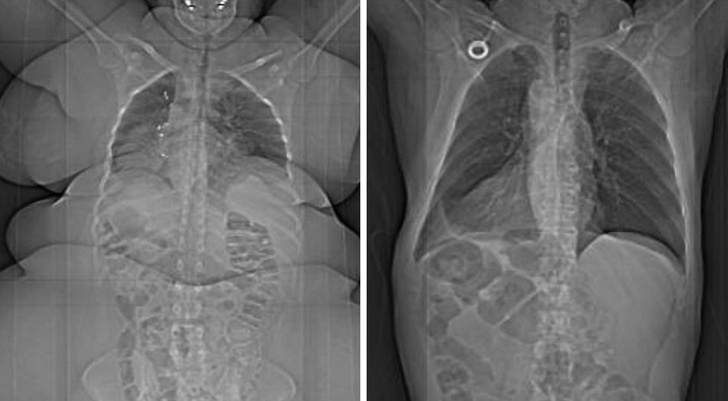

15. Sự khác biệt giữa cơ thể người thừa cân và cơ thể người bình thường thông qua máy chụp X-quang.

![]() |